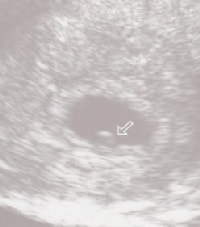

超音波検査では、妊娠4~5週ごろに赤ちゃんの入った袋(胎嚢)が見えてきます。それから約1週間後に胎嚢の中に胎芽(妊娠7過までの赤ちゃん)が見え、心拍も確認できるようになります。ここで初めて妊娠が成立したことになります。

ただし、最終月経から算出した妊娠週数にズレがある場合は、この限りではありません。最終月纏が予定どおり来ても、排卵や受精が遅れると、実際の妊娠週数よりも早く数えていることがあります。「むう妊娠6週のはずなのに、胎嚢が見えない」などといたずらに心配せず、次週の診察を待ちましょ実際の妊娠週数は、赤ちゃんの個体差が最も小さい妊娠9~10週ごろに、赤ちゃんの頭からおしりまでの長さ(頭殿長)を測って算出します。このとき、出産予定日も確定します。